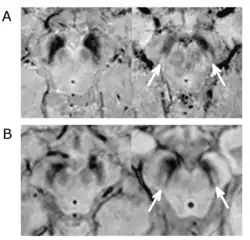

Cette boucle motrice serait notamment constituée d'une voie directe, comprenant le putamen et ses projections GABAergiques sur les parties motrices du GPi et de la SNr ; ainsi que d'une voie indirecte comprenant le putamen et ses projections GABAergiques médiées par les sorties des ganglions de la base de manière indirecte, c'est-à-dire au travers d'une séquence de connexions impliquant le GPe et le STN. Dans ce cadre, une augmentation de l'activité de la voie indirecte est susceptible de mener à une hypokinésie, voire à une akinésie totale, par augmentation de l'inhibition pallidothalamique. Des études menées sur le singe lésés par injection de MPTP (une neurotoxine détruisant spécifiquement les neurones dopaminergiques de la SN[24]) affichent que ceux-ci ont une activité neuronale tonique troublées dans les deux sections du globus pallidus[25]. On observe chez eux une augmentation de l'activité neurale tonique au sein du GPi, tandis que dans le GPe les décharges toniques diminuent. Cette fluctuation de l'activité tonique représenterait une baisse de la sélectivité des informations au sein du circuit[24]. De plus, après injection, on observe également qu'au sein du GPi plus de neurones ont une activité neuronale phasique pour les mouvements volontaires ainsi que pour les stimulations proprioceptives[26].